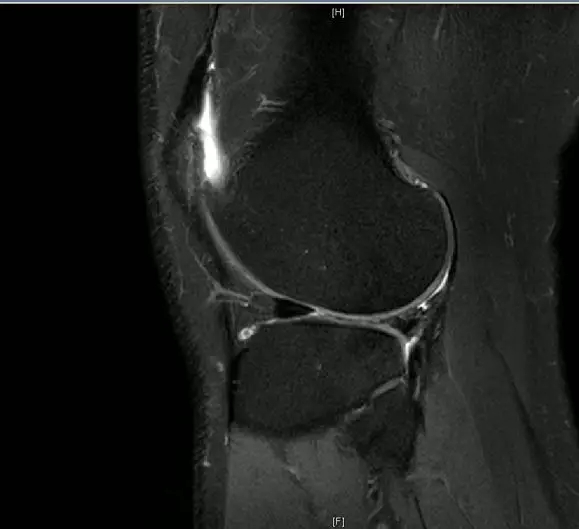

前交叉韧带断裂

从这个病例我们可以看到明显的股骨外髁骨擦伤,韧带的形态是中断的,大片的渗出病变,并且以胫骨平台的夹角变小,下止点可见部分信号增高,上止点可见大片的渗出病变,缺乏韧带止点应有的形态和张力,轴位片也可以看到内外上止点信号改变。所以这个病例考虑前交叉韧带断裂。